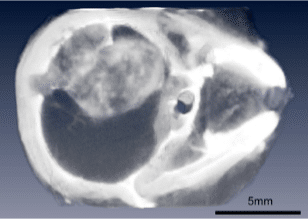

Curing brain cancer in mice with Gold NPs + RT

Brain tumors could be imaged at high resolution (Fig. 3) and combined with RT produced 50% long-term survival (Fig. 4).

Read the article: “Gold nanoparticle imaging and radiotherapy of brain tumors in mice” https://doi.org/10.2217/nnm.12.165